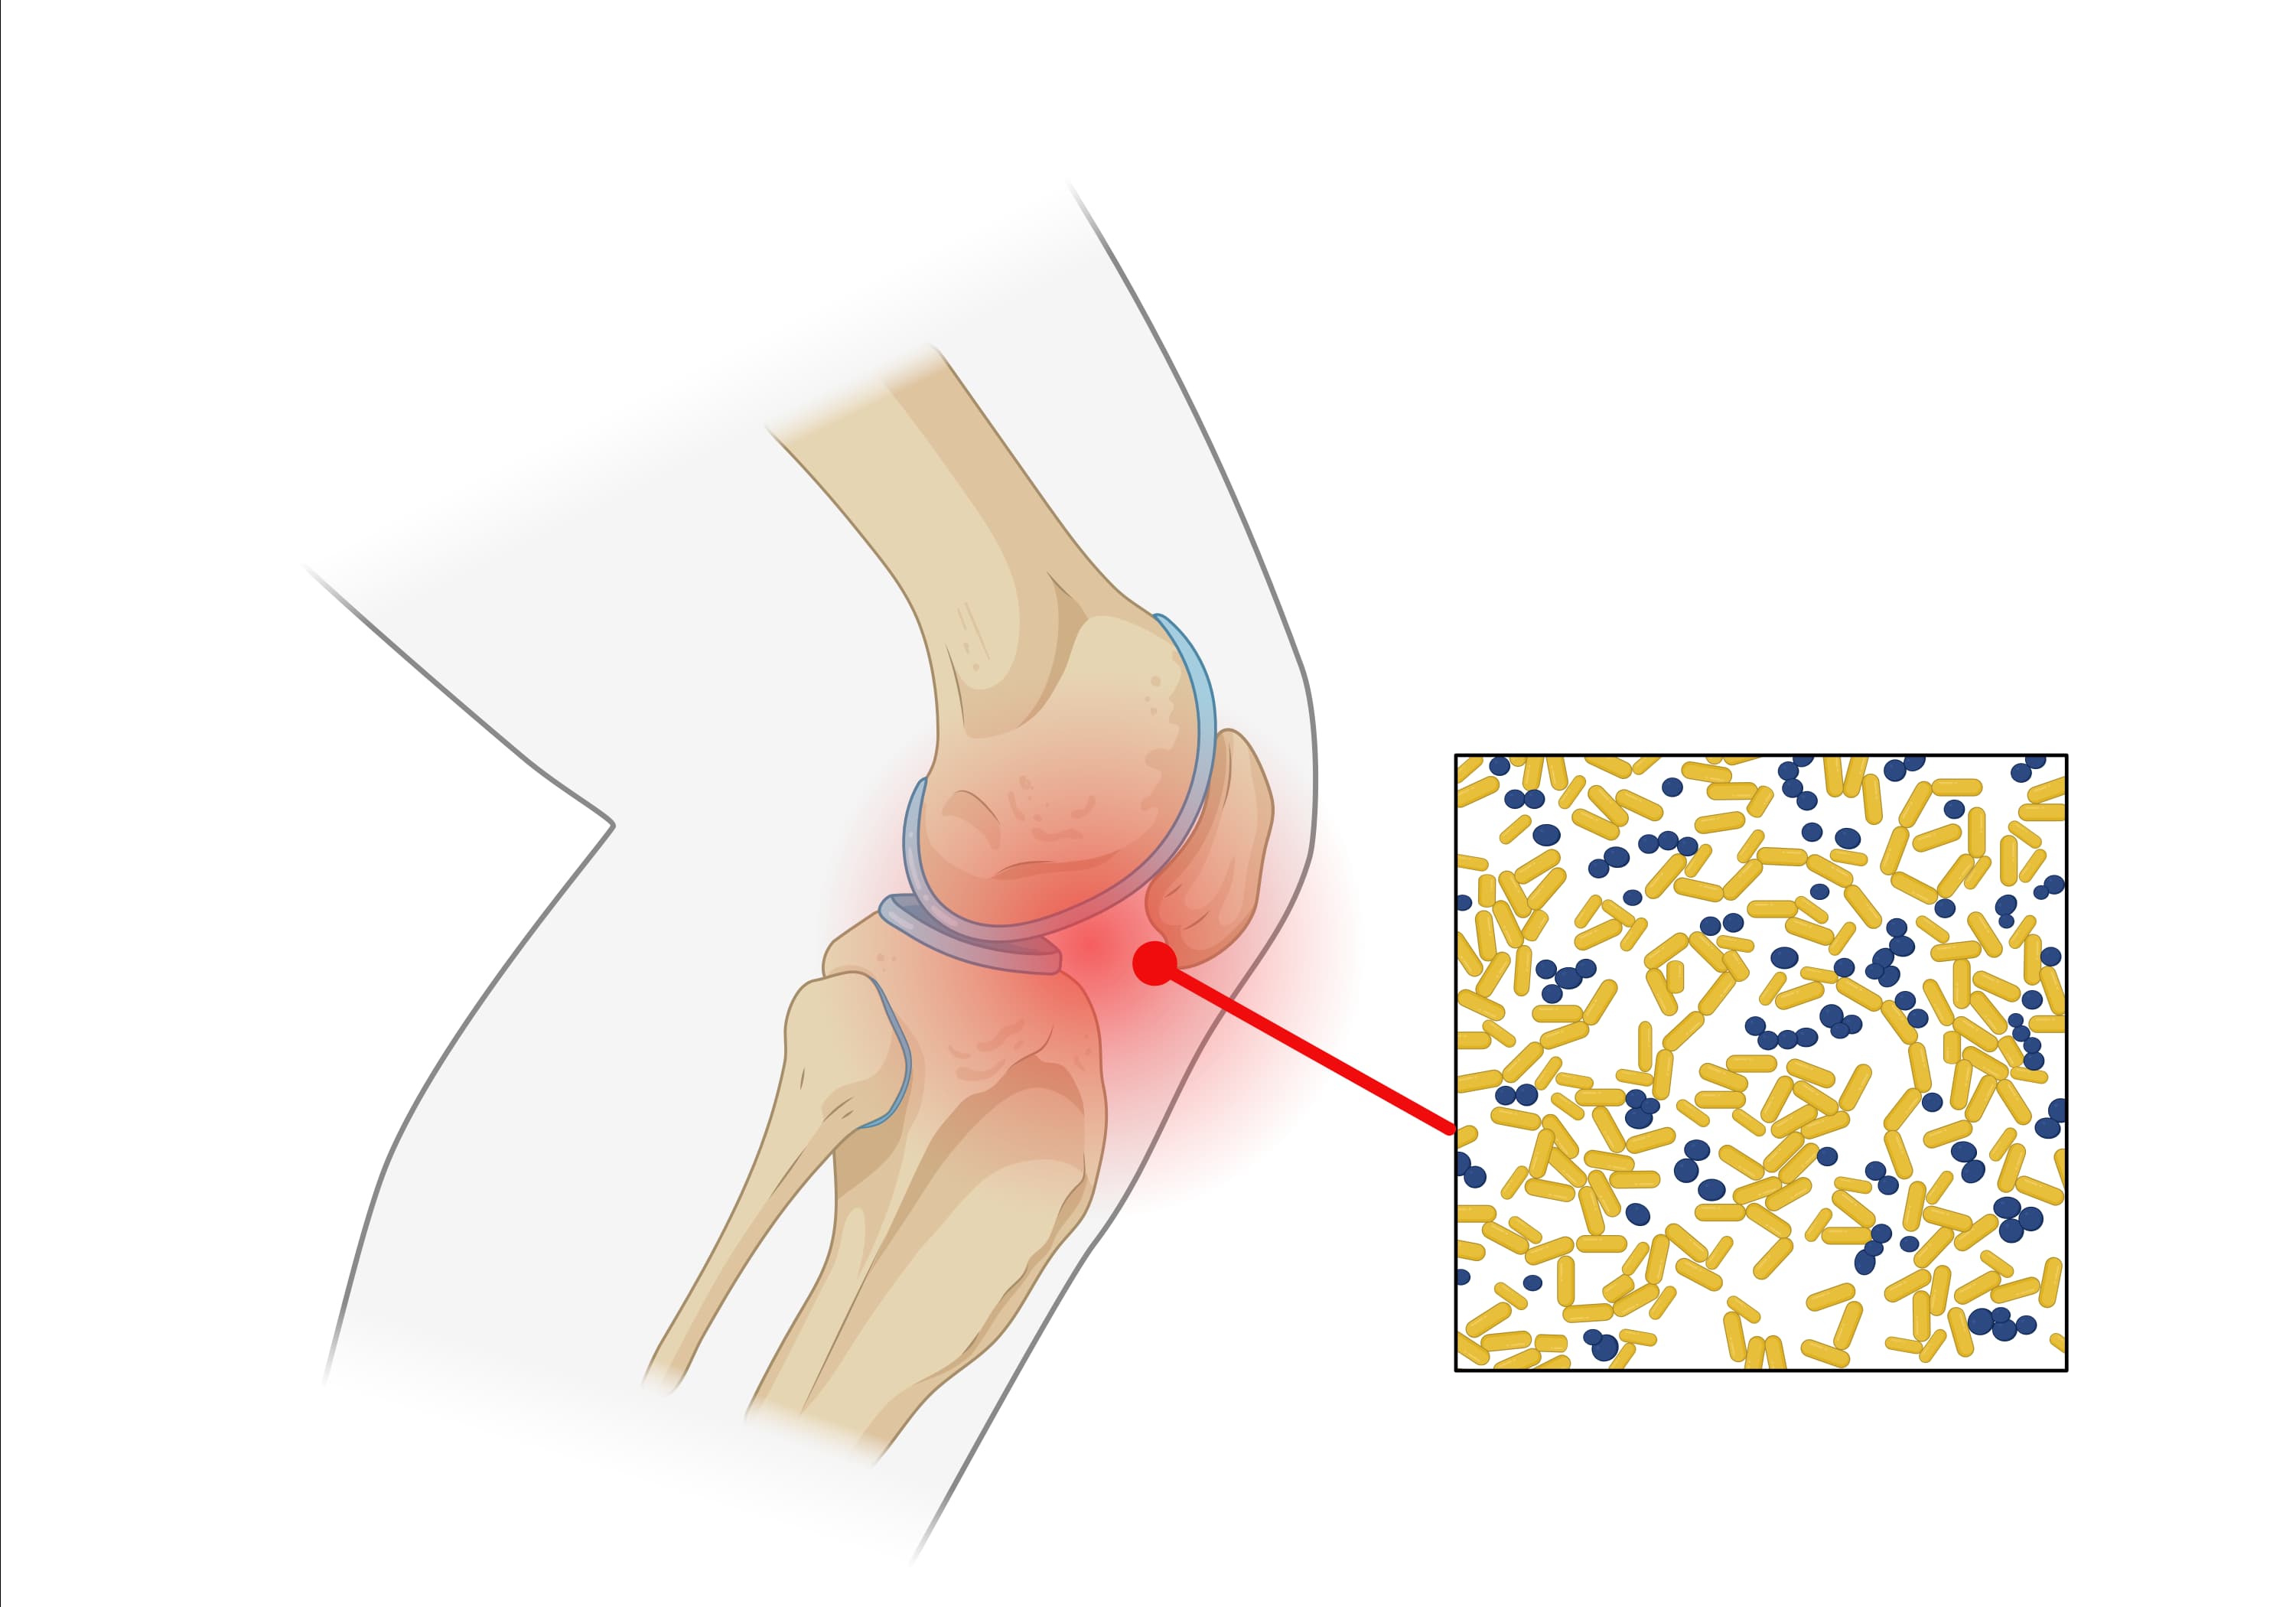

Explore our collection of statistical models designed to predict the probability of septic hip arthritis or septic knee arthritis.